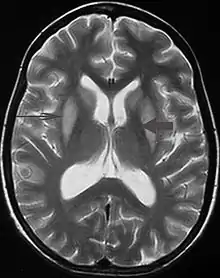

قد يكون من الصعب التشخيص باستخدام تقنيات التصوير التقليدية. ويكون أكثر وضوحا في صور الرنين المغناطيسي أكثر منه في الأشعة المقطعية.